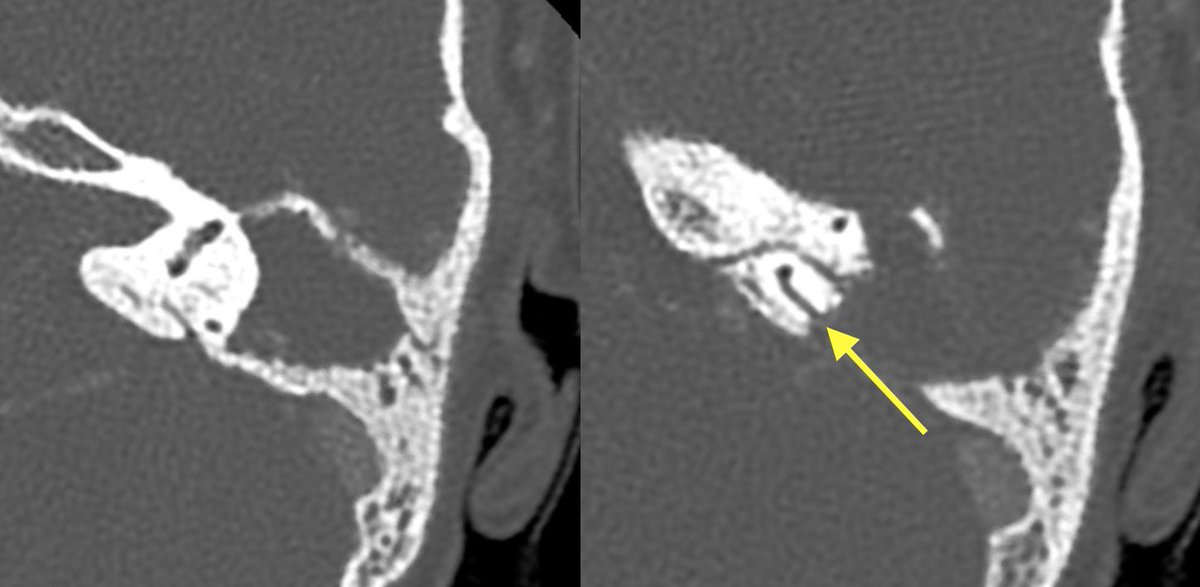

Initial T bone CT:

▶️Coalescence of mastoid air cells

▶️diffuse dehiscence of Tegmen tympani

▶️Middle ear ossicle erosions

▶️dehiscence of the roof of the EAC

▶️dehiscence of semicircular canals and tympanic segment of facial nerve

With findings this extensive it can be difficult to differentiate cholesteatoma from coalescent otomastoiditis